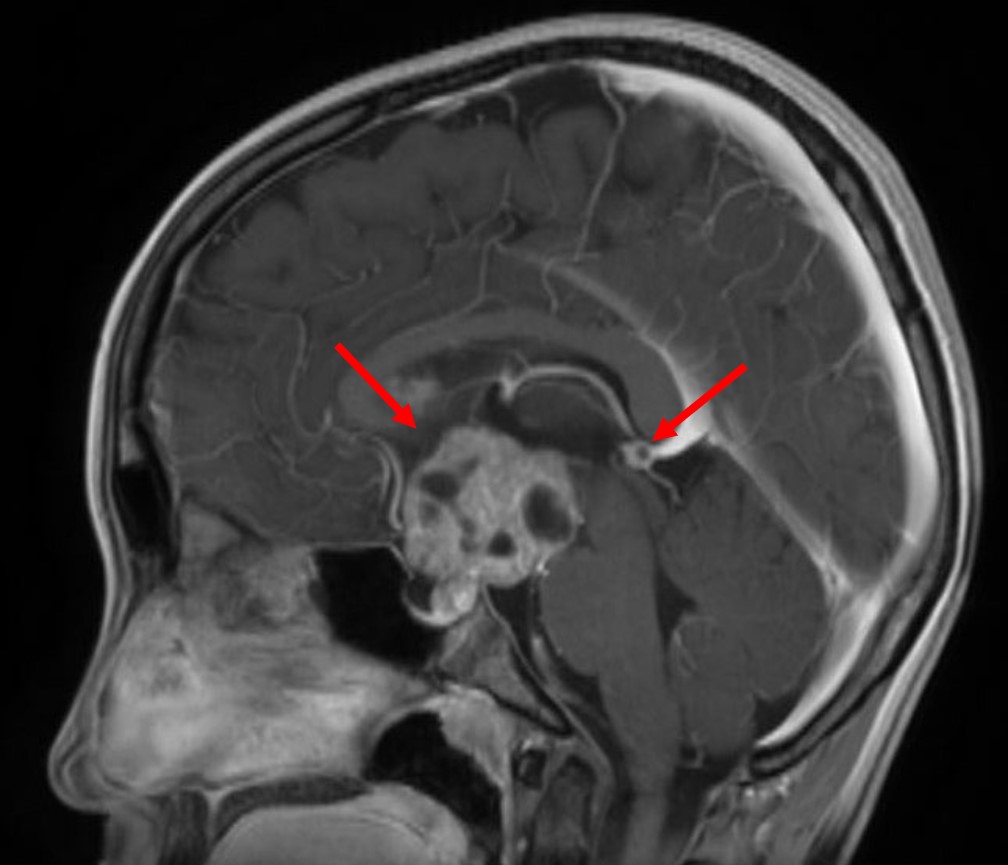

胚腫のMRI。2箇所に腫瘍を認める。

この腫瘍は松果体部(50%)と神経下垂体部(30%)にできやすい腫瘍で、その他にも大脳基底核、視床、脳幹部、小脳にも発生することがあります。また、腫瘍の種類によって発生しやすい場所が異なります。松果体部には男児に圧倒的に多く女児には少ないのですが、神経下垂体部には性差はありません。